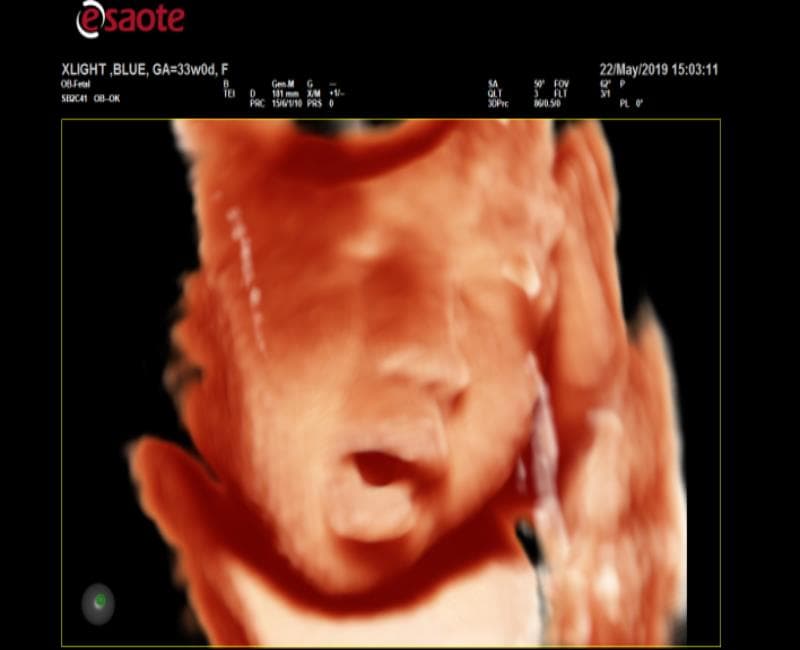

may sieu am mylab x6

XLight - phần mềm siêu âm 3D/4D chuyên sâu cho mặt thai nhi mịn, chân thật nhờ công nghệ bố trí nguồn sáng ảo và khả năng tái tạo bề mặt.

XLight với chế độ cột sống của thai nhi.